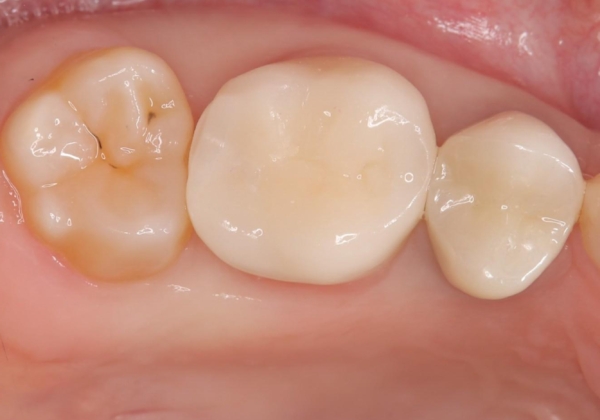

オールセラミッククラウンの膨隆で下部鼓形空隙を適切な大きさに調整しました。